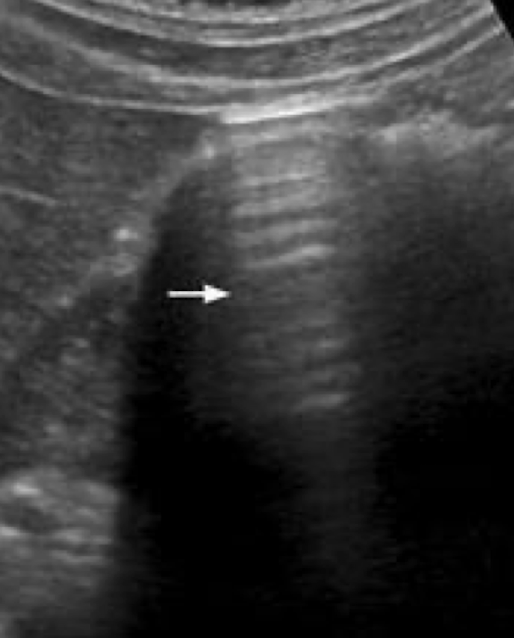

SONO: emphysematous cholecystitis

bright echoes along anterior GB wall with “ring down” or “comet tail” artifact

gallstones may not be present

??

emphysematous cholecystitis

“ring down” artifact